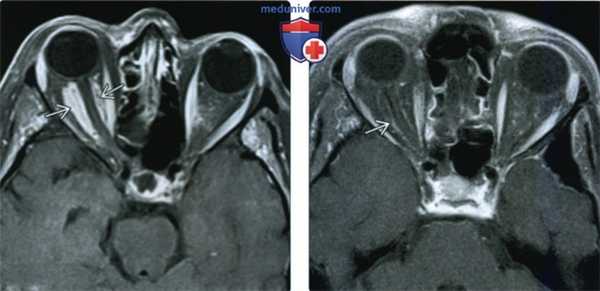

(Слева) У пожилой женщины с нейрооптикопатией при МРТ Т1ВИ FS c Ky в аксиальной проекции внутри мышечного конуса визуализируется объемное образование, окружающее влагалище зрительного нерва. На основании клинических проявлений был выставлен предположительный диагноз менингиома.

(Справа) У этой же пациентки два года спустя при аксиальной МРТ Т1ВИ FS с КУ наблюдается почти полное спонтанное разрешение образования внутри мышечного конуса, вдоль влагалища зрительного нерва видна лишь узкая минимально контрастная полоска. Предположительный диагноз: идиопатическое воспаление глазницы.

(Слева) При МРТ Т1ВИ FS c КУ в аксиальной проекции у пациента с болезненным экзофтальмом определяется объемное образование глазницы, поражающее наружную прямую мышцу и ткани внутри мышечного конуса. Обратите внимание на распространение идиопатического воспаления через верхнюю глазничную щель в переднюю часть кавернозного синуса.

(Справа) При МРТ Т1ВИ FS с КУ в корональной проекции у этого же пациента видно, что объемное образование распространяется в полость черепа и прорастает в левый кавернозный синус. Распространение идиопатического воспаления глазницы в кавернозный синус - наиболее часто встречающаяся локализация внеглазничного поражения.